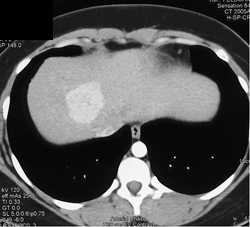

Focal Nodular Hyperplasia (FNH)